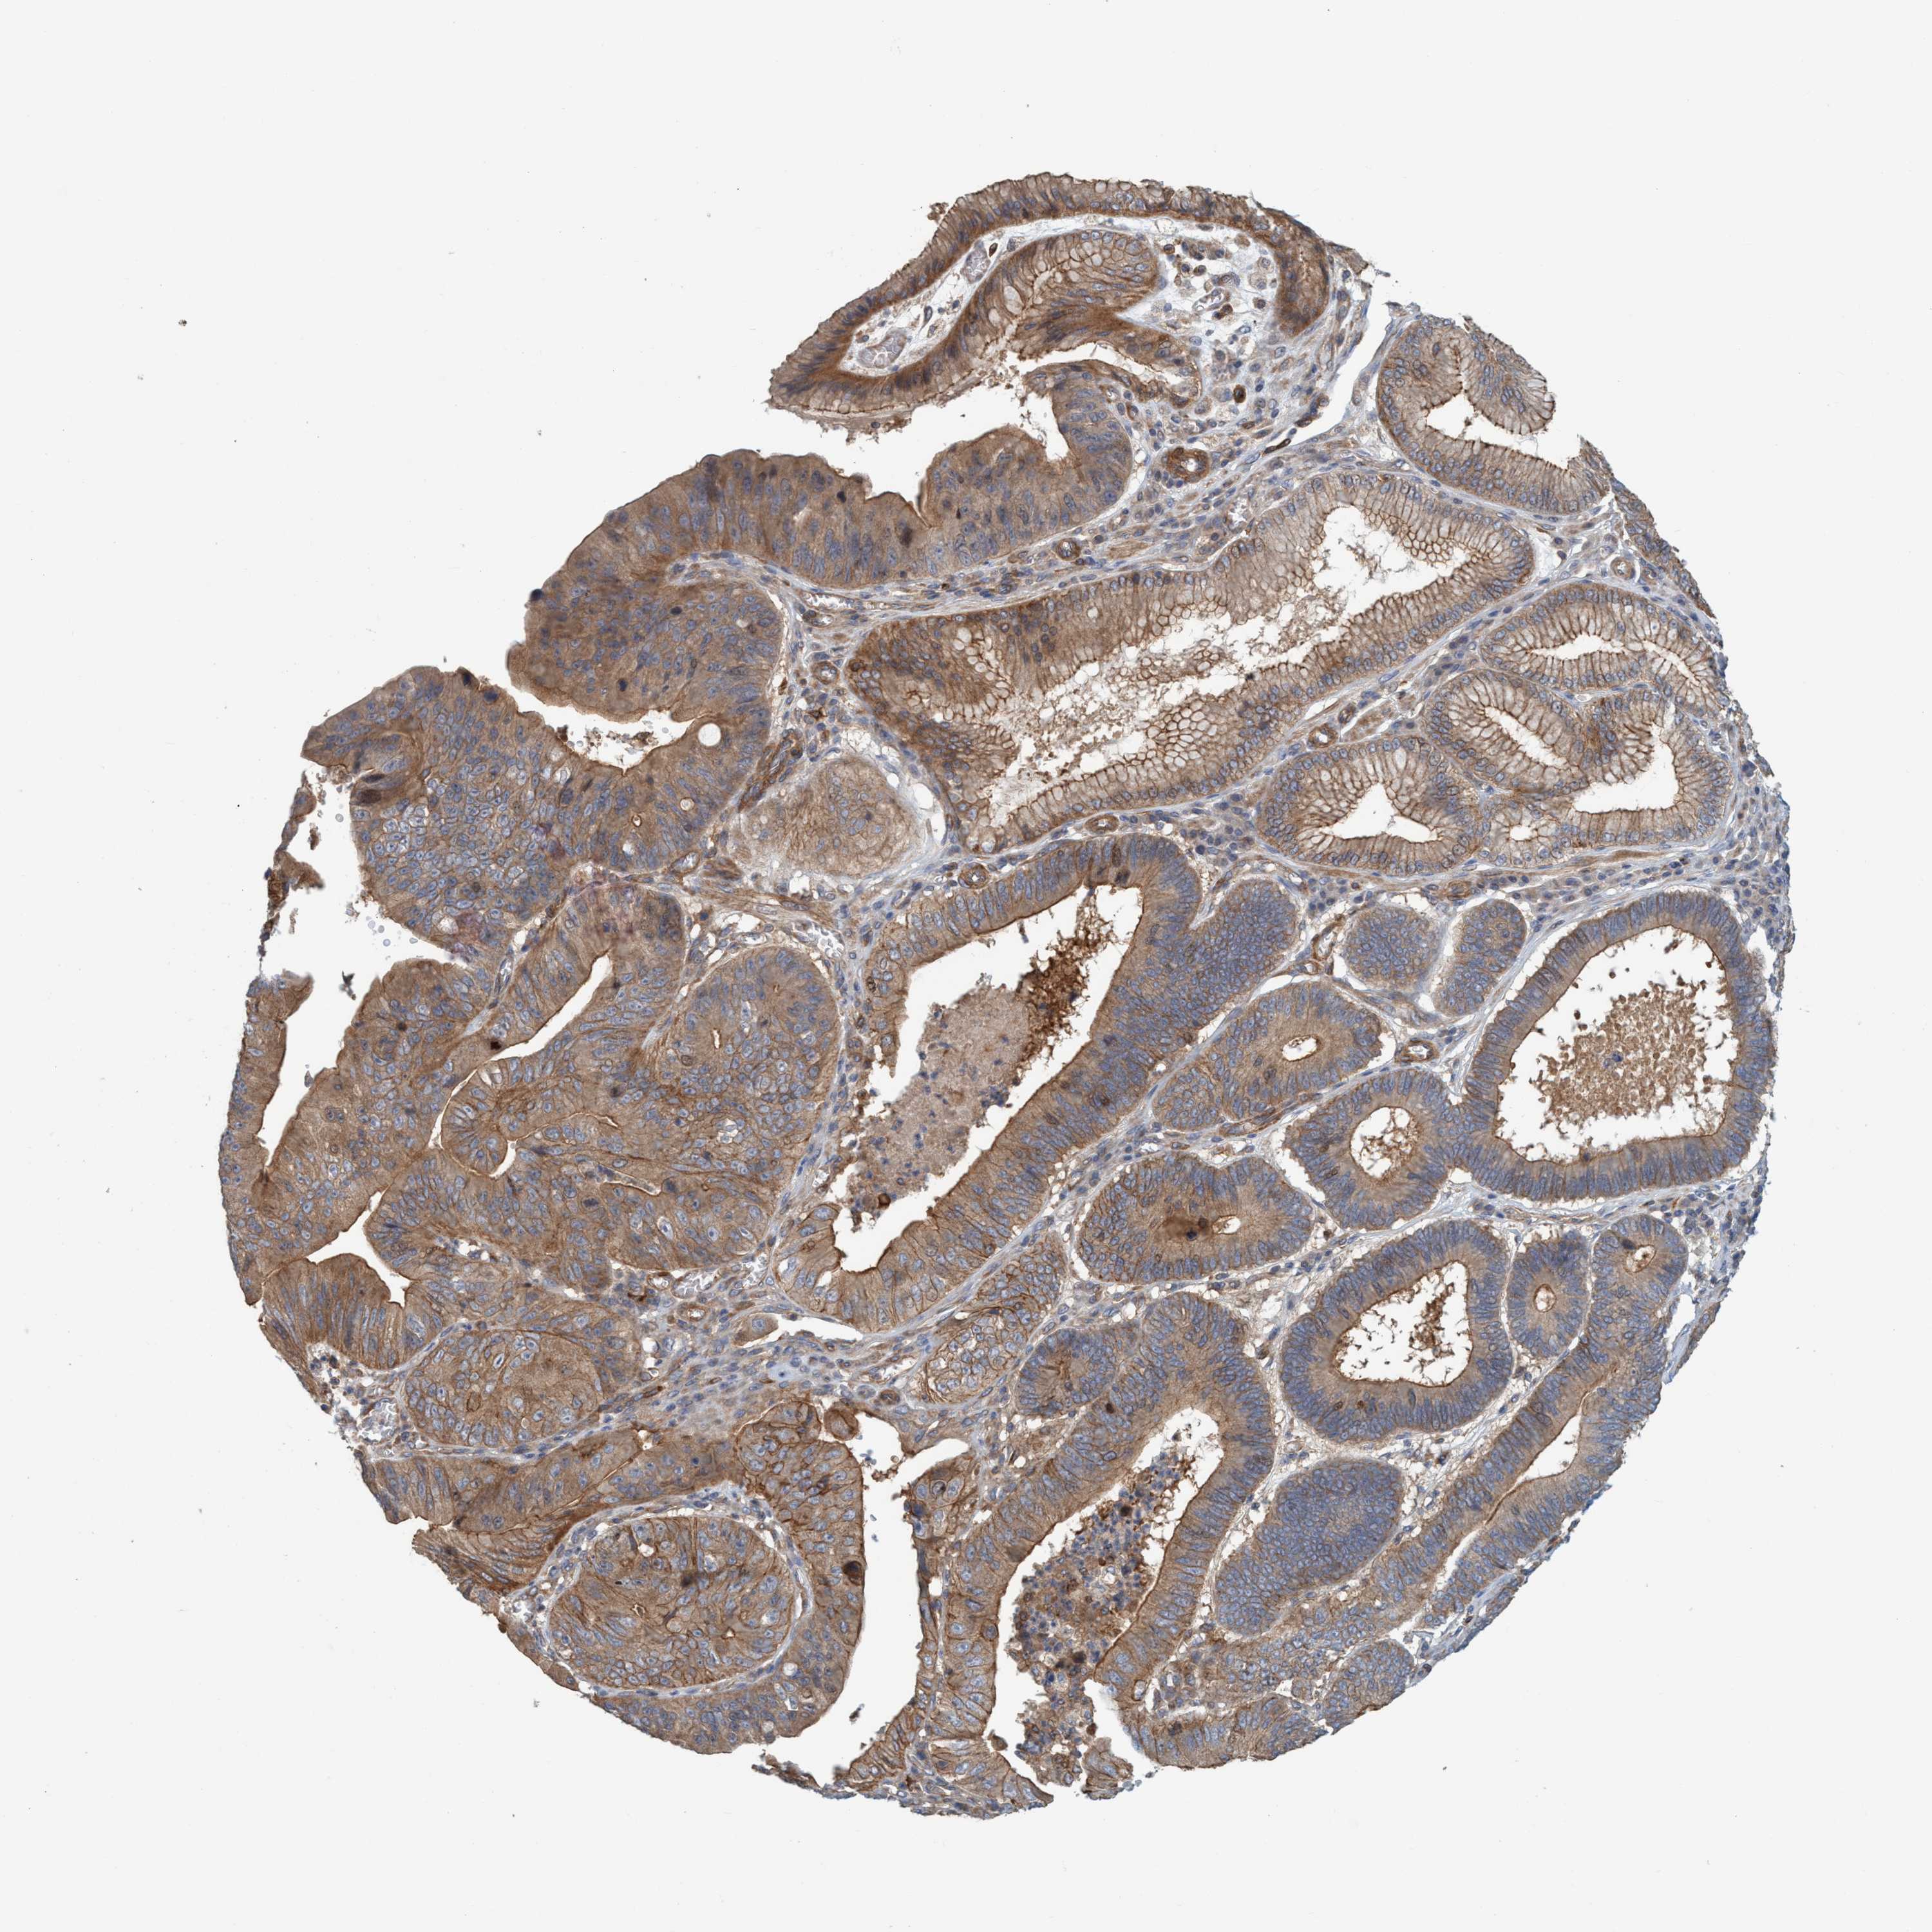

STOMACH CANCER - Protein expressioni

A mouse-over function shows sample information and annotation data. Click on an image to view it in a full screen mode. Samples can be filtered based on level of antibody staining by selecting one or several of the following categories: high, medium, low and not detected. The assay and annotation is described here.

Antibody stainingi

Antibody staining in the annotated cell types in the current human tissue is reported as not detected, low, medium, or high, based on conventional immunohistochemistry profiling in selected tissues. This score is based on the combination of the staining intensity and fraction of stained cells.

Each image is clickable and will lead to virtual microscopy that enables deeper exploration of all samples and also displays staining intensity scores, fraction scores and subcellular localization as well as patient and tissue information for each sample.

Antibody HPA021421

Antibody HPA021430

Staining

High

Medium

Low

Not detected

Intensity

Strong

Moderate

Weak

Negative

Quantity

>75%

75%-25%

<25%

None

Location

Nuclear

Cytoplasmic/membranous

Cytoplasmic/membranous,nuclear

Adenocarcinoma, NOS